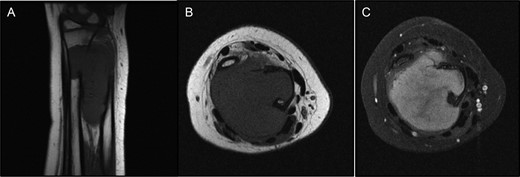

A MRI images revealed a large mass at the level of the distal radial and ulnar metadiaphyses, measuring ∼6 cm craniocaudad, 3.7 cm AP and 3 cm transverse (Fig. 4).

(A and B) T1 MRI showing mass iso-intense to muscle. (C) T2 MRI axial view with overall increased signal intensity, but with a central area of decreased signal.